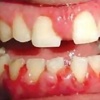

Gingiviit ehk igemepõletik

Gingiviit on hammast ümbritseva igeme põletikuline protsess, mis on tingitud hambakatu kogunemisest ning mis kujuneb välja ebasoodsate lokaalsete ja üldiste faktorite toimel, kusjuures on säilinud igeme terviklik kinnitus hambapinnale ja...

Krooniline gingiviit

Krooniline gingiviit, mida seostatakse katu kogunemisega, esineb enamasti ja on väga tavaline täiskasvanud populatsioonis ning kujuneb välja peale 2-3 nädalast katu ladestumist igemepiirile. Nii nagu on erinevad kõik inimesed on...